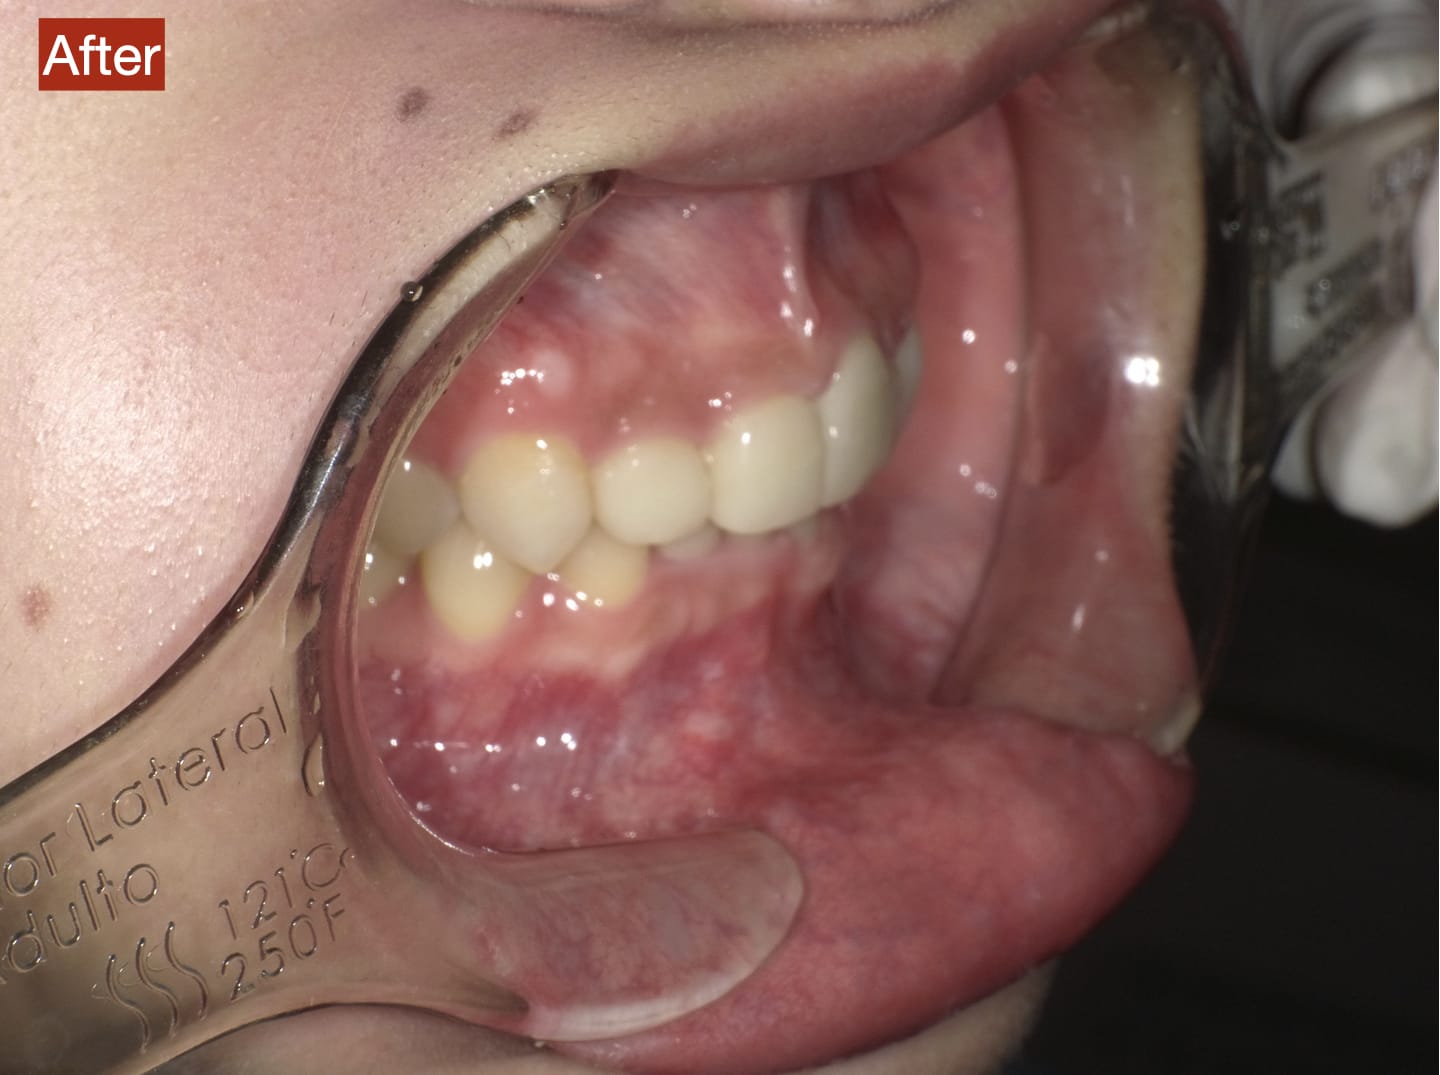

Case029

セラミック矯正の患者様です。

・上下の歯の入れ違い

・正中の歪みと隙間

を主訴にご来院くださいました。

この患者様は若年性歯周炎にかかってしまったため、一生懸命に歯を磨き、口の中は綺麗なのにも関わらず歯茎が下がってしまい、隙間が出来てしまっています。

これは矯正治療で歯の並び方を変えても絶対に無くなりません。

そのため、患者様の主訴を叶えるためにセラミック矯正で治療計画を練りました。

前のクリニックでは「上下一本ずつ抜糸してブリッジで矯正する」という計画だったようですが、

・患者様が非抜歯を希望されていること

・歯を抜かなくても綺麗に並べられそうだったこと

を理由に、当院では上は抜かずにセラミック。下は形態修正だけで対応しました。

この方針変更だけでもお値段も安く、また侵襲(ダメージ)を少なくすることができました。

治療の結果、最低限の侵襲で、見違えるほど綺麗な口元に治療することができ、患者様もとても喜んでくださいました。

主訴とご希望によって、ワイヤー矯正、マウスピース矯正、セラミック矯正のどの矯正が適しているかは異なります。

当院では上記全ての治療法に対応することができるので、主訴とご希望に沿った方法で治療することが可能です。

カウンセリングにてご希望をお伺いした後、一つ一つの治療の違い、当院のおすすめをご紹介いたしますので、ご希望の治療方法をお選びいただけます。

歯並びなどお口元にお悩みのある方、より綺麗な口元になりたい方はぜひ一度ご相談ください。

【主訴】

・上下で入れ違っている前から2本目の歯のすれ違いを治したい。

・清潔感のある白さで明るい綺麗な口元にしたい

・歯の隙間を無くしたい

【ご要望、ご状況】

・歯を抜かずに治したい

・前医では上下1本ずつ抜歯をして、ブリッジで上3本、下3本の計6本を治すことを提案された。

【今回の治療法】

・右上の犬歯から左の前歯までの計4本をジルコニアセラミックで治療

・色は自分の歯よりやや白いくらいでホワイトニングをしてもしなくても大丈夫なくらいの白さ

・歯は抜かない

・右下の歯は形態修正だけで対応

・歯茎のラインを歯肉整形術で整える